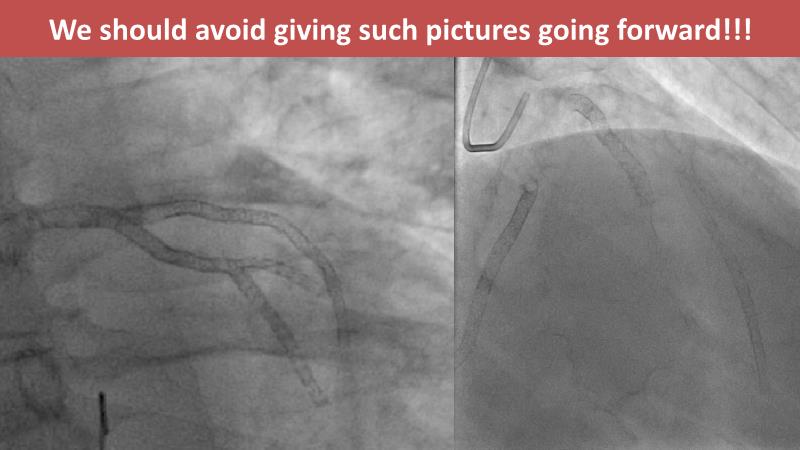

- To learn from the real world registries and complex cases to understand the practical implications and potential of the device in diverse patient population